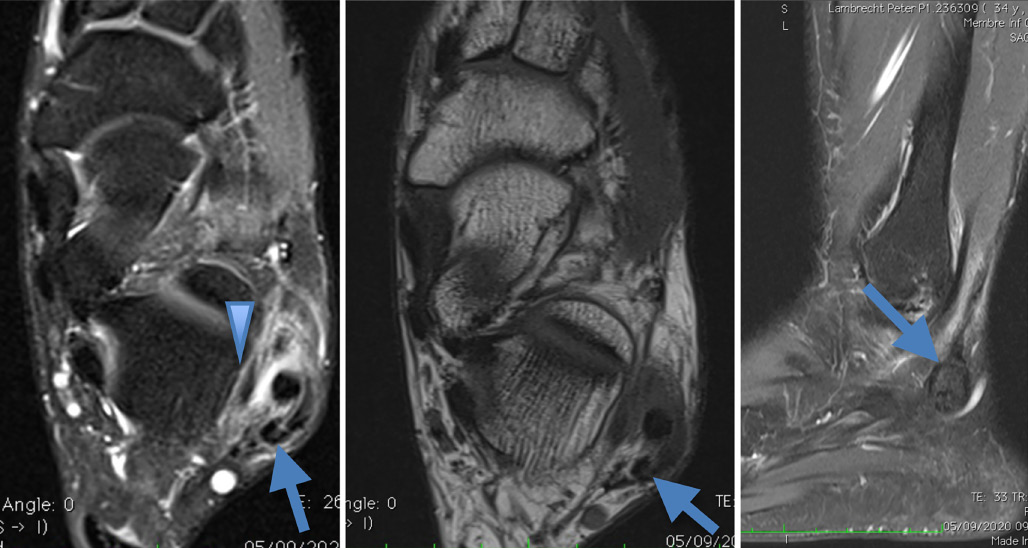

Thrombose de la veine plantaire latérale